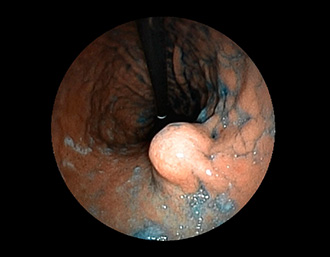

症例5:胃腺腫(84才女性)

胃角部に、大きさ10mm強のなだらかな粘膜隆起を認める。生検:Tubularadenoma with moderate atypia.Group 3。経過観察中。

(インジゴカルミン散布画像)